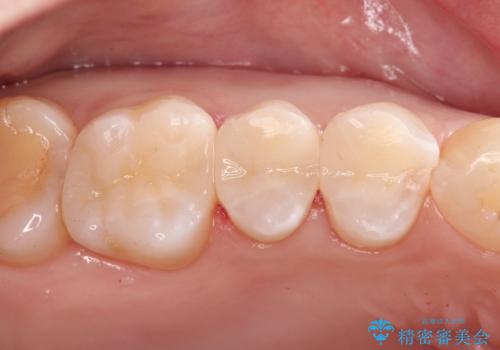

- 金属の詰め物を外して、セラミックインレーを入れたいと来院された患者様です。

奥歯に虫歯も認め、3歯の治療を来院回数2回で終了で終了しています。

当院でのセラミックインレーはすべてe-maxと呼ばれる高強度セラミックにて製作されます。

また、製作方法もプレスと呼ばれる方法を用いることで精度を高めています。